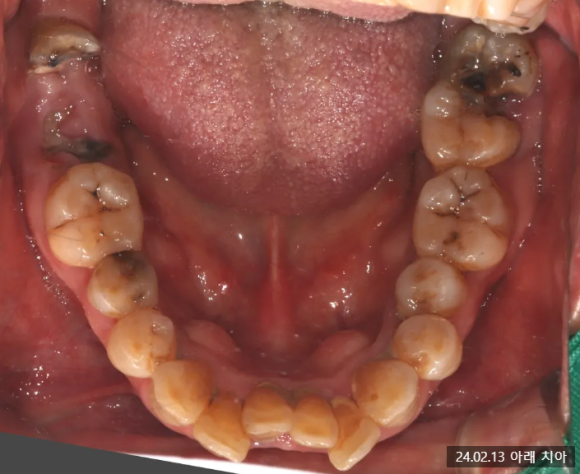

내원 당시 상황

환자분은 오래전 상실한 치아로 인해 교합이 맞지 않고, 왼쪽 아래 어금니는 흔들림이 심해 식사를 제대로 하실 수 없는 상태에서 저희 치과를 찾아주셨는데요.

좀 더 정밀한 검사를 통해 다음과 같은 문제를 확인할 수 있었습니다.

2024.02.13 초진 파노라마, (사진상 좌.우 반대)

- 충치 문제: 오른쪽 어금니(사진상 왼쪽)는 뿌리까지 충치가 심해 발치가 필요한 상태였습니다.

- 잇몸뼈 부족: 왼쪽 위 어금니(사진상 오른쪽)는 이 뽑은 후 잇몸뼈가 1~2mm밖에 남지 않을 것으로 예상되었는데요.

이 경우 임플란트 고정이 어렵기 때문에 뼈 이식과 상악동 거상술이 필요했습니다.

- 교합 불안정: 치아가 빠진 자리를 오랫동안 방치해 배열이 틀어지면서 치아 맞물림 상태가 매우 불안정해졌습니다.

2024.02.13 발치 전